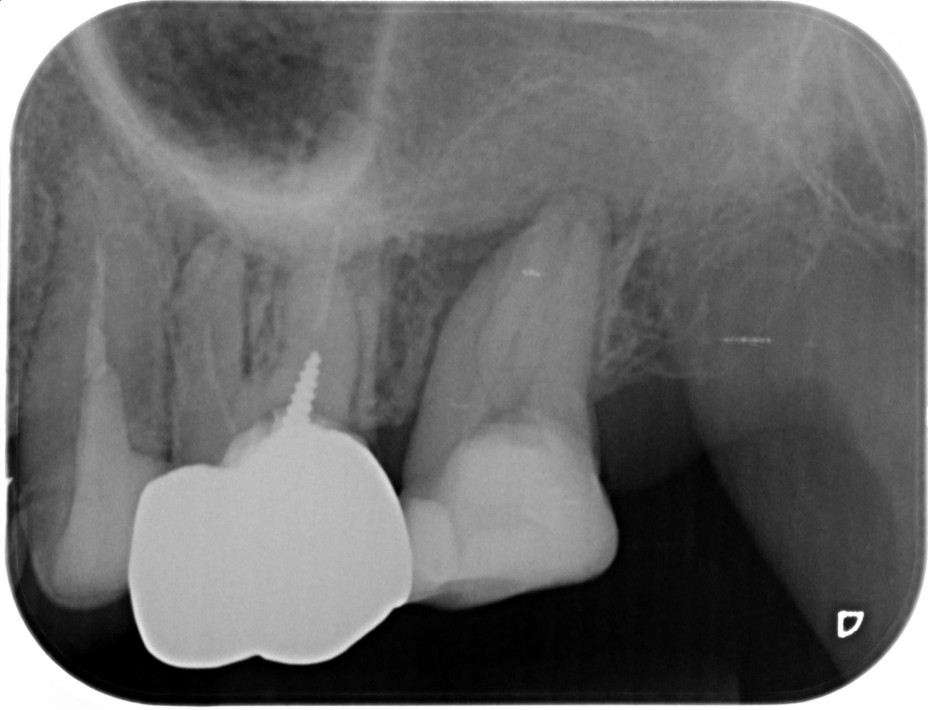

| 患者様データ | 60代 男性 |

| 来院時の主訴 | 「右下の歯が噛むと痛い。」 |

| 医院の診断 | セメント質剥離を併発した歯根破折 |

| 治療費 | 総額:270,000円(税抜) 【内訳】 精密根管治療80,000円+歯牙再植100,000円、ファイバーポストコア20,000円、ダイレクトボンディング治療70,000円 |

すでに歯根破折を起こしている歯のため、かなりシビアな状態ではありますが、患者様の強い要望により歯牙再植を応用した方法により歯の保存を行いました。 |